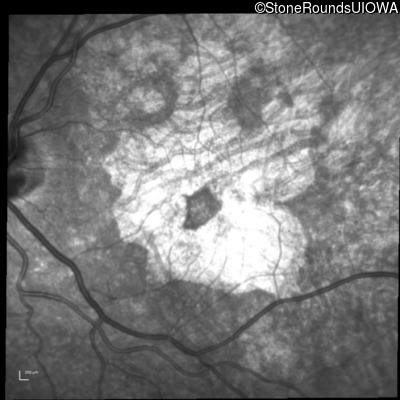

Blue Autofluorescence - Right - 20/32 +2

Exemplar